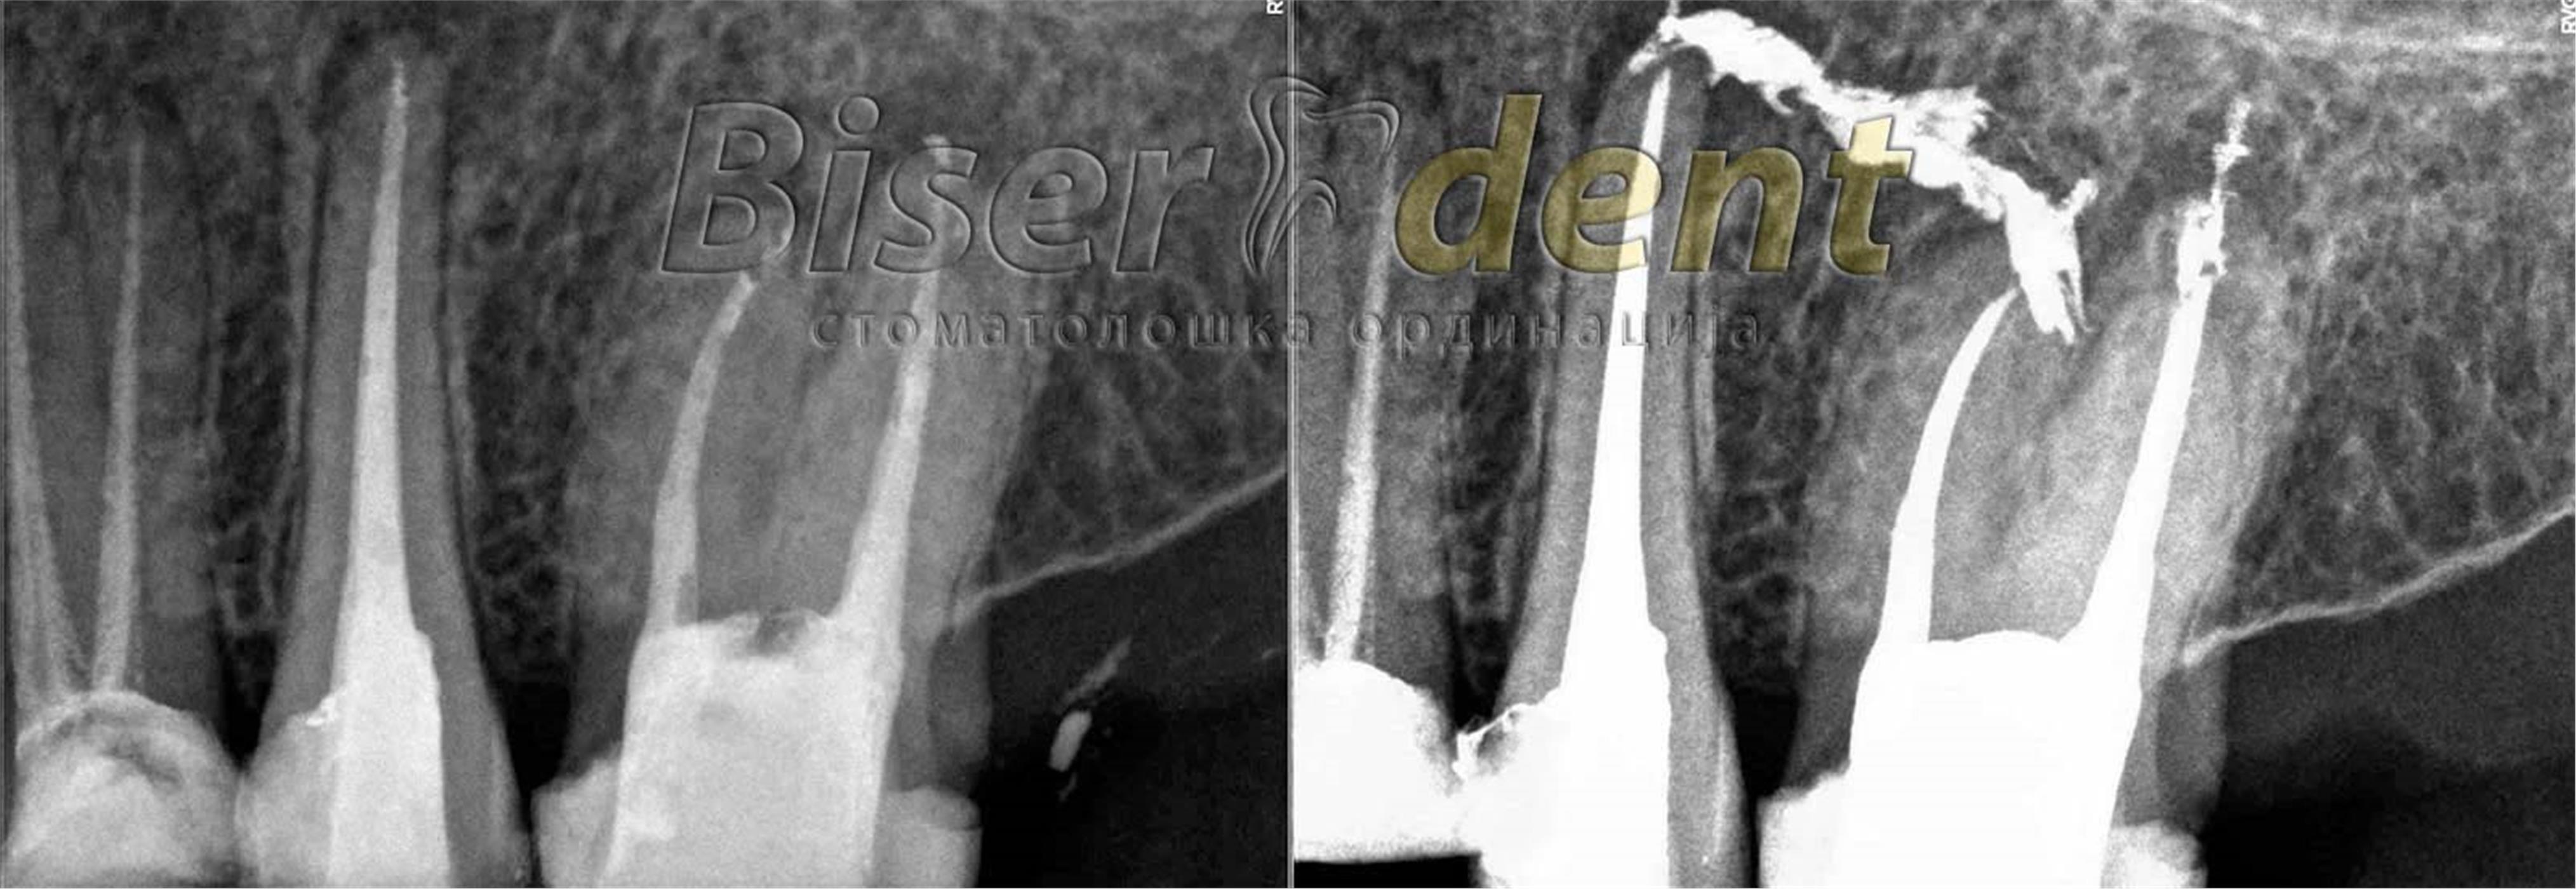

РЕВИЗИЈА